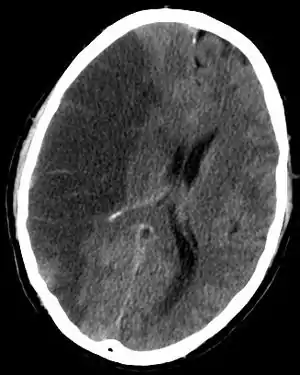

| سیتی اسکن قسمتی از مغز که ایسکمیک ناشی از سکته مغزی را نشان میدهد. | |

درمان اولیه پس از وقوع یک سکته مغزی شامل تحت نظر گرفتن دقیق فرد و انجام اقدامات پرستاری برای محافظت راه تنفسی او میباشد. اگر در سی تی اسکن دیده شد که یک لخته خون در شریان وجود دارد، باید فوراً با استفاده از داروهای ترومبولیتیک اقدام به حل کردن آن نمود. این درمان ممکن است باعث بهبود عواقب سکته مغزی بشود اما در هر موردی نباید آن را بکار برد، زیرا باعث افزایش خطر بروز خونریزی در مغز میشود.